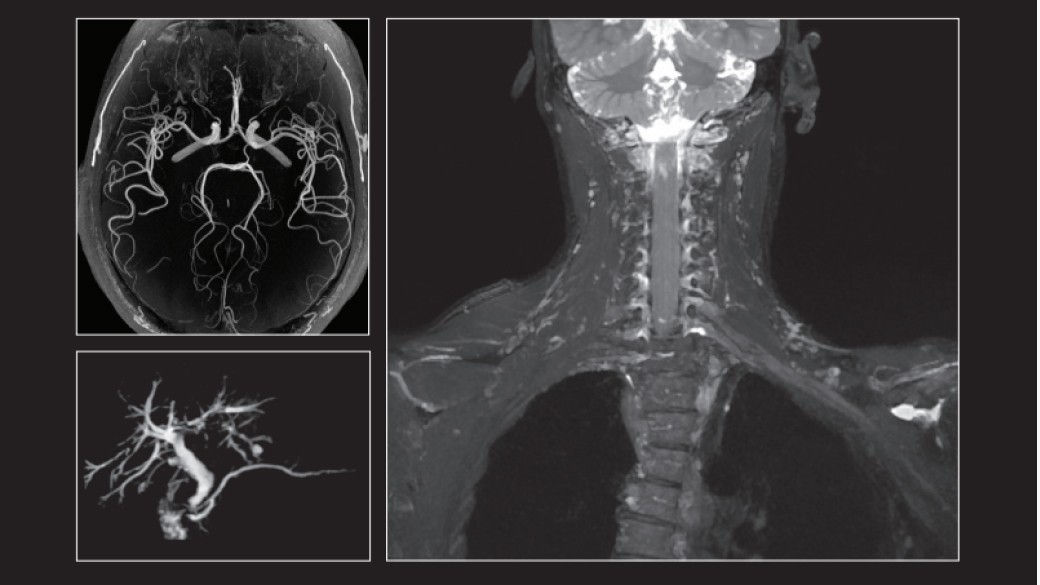

Brain imaging (MRI, PET/MR, PET/CT) is a critical component of a confident Alzheimer’s diagnosis.

Structural imaging by MR is primarily used to rule out other causes of Alzheimer’s symptoms

mri-solutions-desktop

Visualization of brain amyloid is critical to identifying patients with Alzheimer's disease.